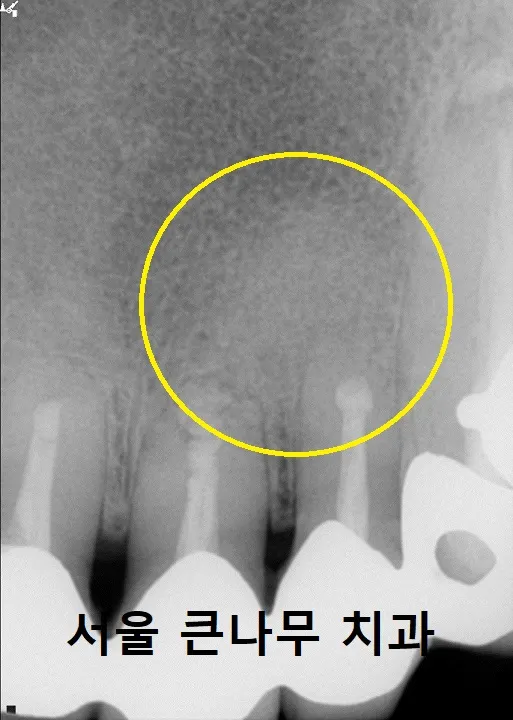

X-ray 사진을 통해 전과 후를 비교해 보았습니다.

치료전 염증 상태(왼), 치근단절제술 후 뼈이식된 모습(오)

왼쪽 사진이 치료전 고름 주머니가 차있는 상태이고, X-ray 상에서 까맣게 보이는 상태입니다.

오른쪽 사진이 치근단절제술 후 뼈이식이 완료된 상태로, 염증을 모두 긁어내고 그 자리를 인공뼈로 채워 넣은 상태입니다.

수술은 성공적으로 완료가 되었고, 이 상태로 수술 부위가 잘 아물 수 있도록 기다려 주었습니다.